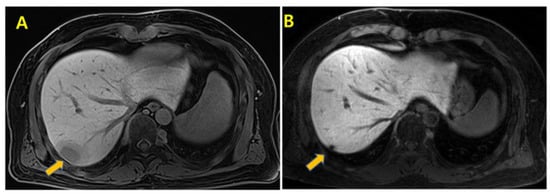

2. Case Presentation